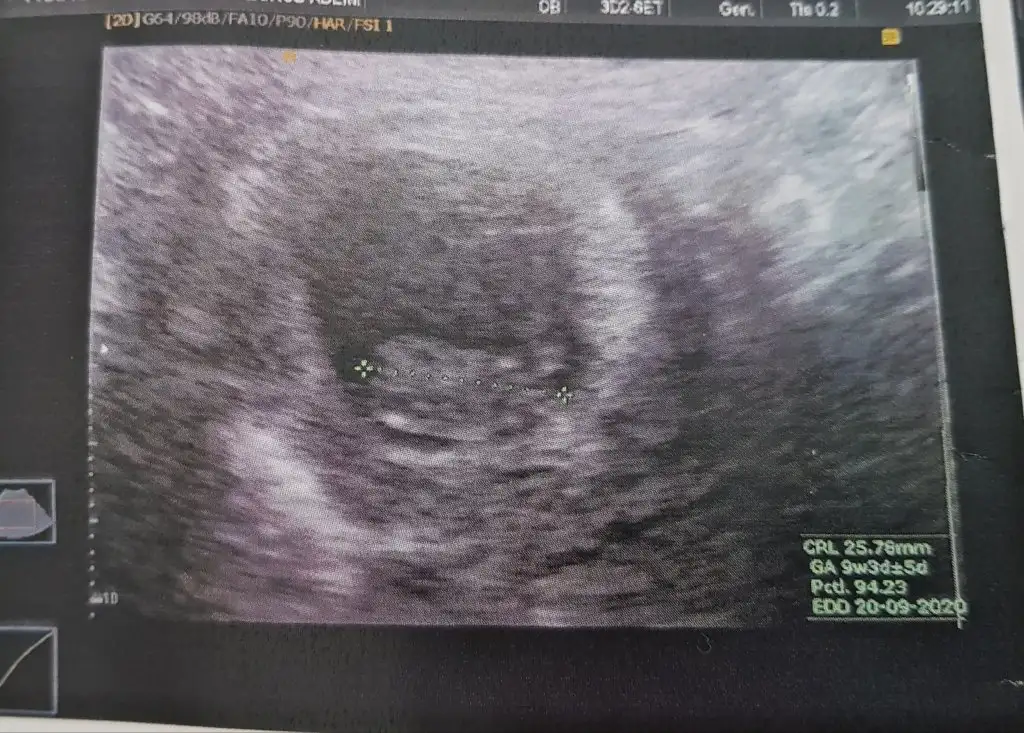

Karından ise erkek nub için 11 yada 12 hafta usg paylaşın10+3 Suan burda 7 haftalik sizce nedir arkadaslar? Bu arada cok tatli telaslar hepimiz icin Allah sagsaglim kucagimiza almayi nasip etsin insallah

Buna göre erkek karından bakıldıysa nub için 11 yada 12 hafta paylaşınBanada tahmin yaparmisiniz 8 haftalik